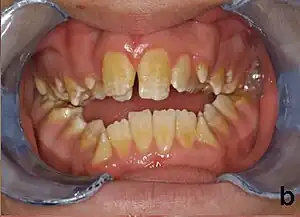

Amelogenesis imperfecta (AI) is a congenital disorder which presents with a rare abnormal formation of the enamel[1] or external layer of the crown of teeth, unrelated to any systemic or generalized conditions.[2] Enamel is composed mostly of mineral, that is formed and regulated by the proteins in it. Amelogenesis imperfecta is due to the malfunction of the proteins in the enamel (ameloblastin, enamelin, tuftelin and amelogenin) as a result of abnormal enamel formation via amelogenesis.[3]

People afflicted with amelogenesis imperfecta may have teeth with abnormal color: yellow, brown or grey; this disorder can afflict any number of teeth of both dentitions. Enamel hypoplasia manifests in a variety of ways depending on the type of AI an individual has (see below), with pitting and plane-form defects common.[4] The teeth have a higher risk for dental cavities and are hypersensitive to temperature changes as well as rapid attrition, excessive calculus deposition, and gingival hyperplasia.[5] The earliest known case of AI is in an extinct hominid species called Paranthropus robustus, with over a third of individuals displaying this condition.[6]

- Type 3 - Hypocalcified

- Enamel defect due to malfunction of enamel calcification, therefore enamel is of normal thickness but is extremely brittle, with an opaque/chalky presentation. Teeth are prone to staining and rapid wear, exposing dentine. Condition is of autosomal dominant and autosomal recessive pattern. Enamel appears less radioopaque compared to dentine on radiographs.

Preventive and restorative dental care is very important as well as considerations for esthetic issues since the crown are yellow from exposure of dentin due to enamel loss.[5] The main objectives of treatment is pain relief, preserving patient's remaining dentition, and to treat and preserve the patient's occlusal vertical height.[20]